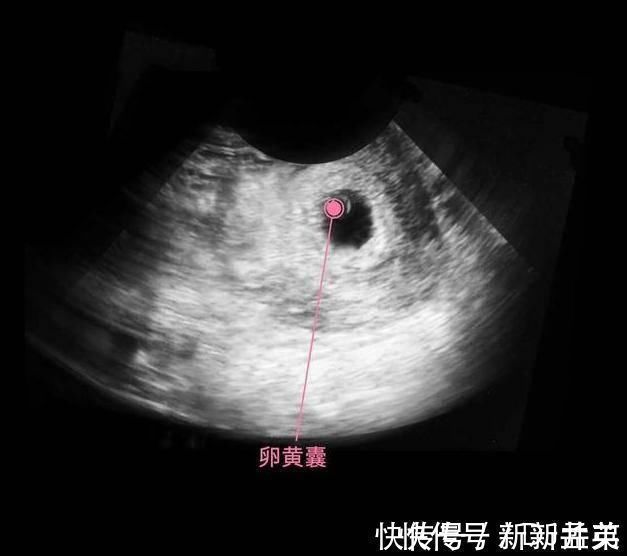

上图是怀孕后,受精卵经过了分裂,形成了细胞团,这个阶段还不能叫胎儿,只能叫胚泡,胚胎开始发育并分泌人体促绒毛性腺激素,不过此时的含量还很少,用验孕棒根本测试不出来。

细胞继续分化,有的分化成胎儿的大脑,有的分化成胎儿的肾脏和肝脏,还有的分化成心脏等,这个时期的宝宝叫做胎芽,依靠着卵黄囊提供的营养,还用不到母体的营养呢,所以此时有了怀孕反应,没有食欲也没有关系,对胎儿发育的影响不大。